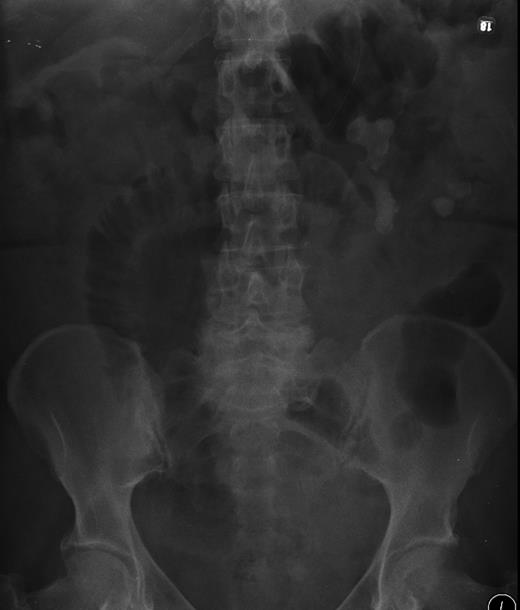

Abdominal X-ray confirmed large bowel obstruction with a cut-off point in the proximal descending colon. A large staghorn calculus was evident in the left kidney with a second smaller well-defined area of calcification just lateral to the renal parenchyma. (Fig. 1)

X-ray showing large left-sided stag horn calculus, with a second adjacent fragment outside the renal parenchyma with evidence of bowel obstruction.